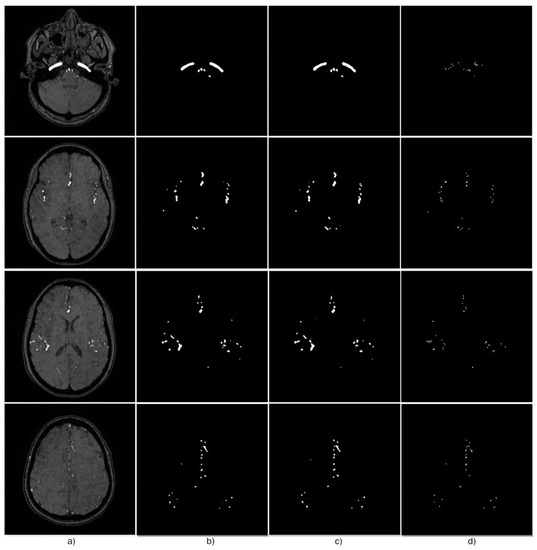

- MRA Images